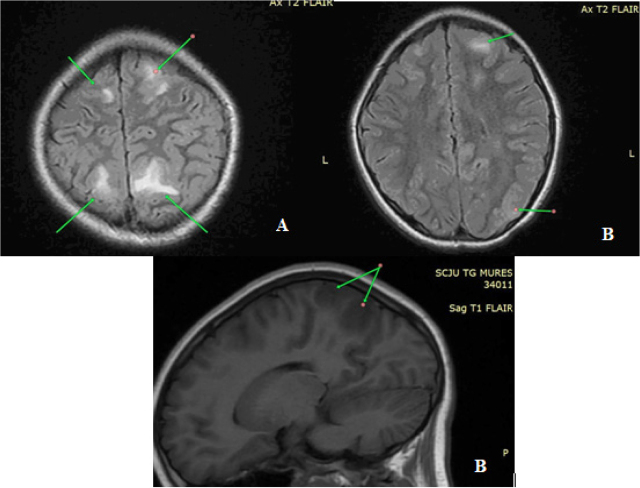

Presentation of case series: In the past six months, we have documented the cases of two patients, aged 15 and 10, both of whom presented with PRES and renal disease. These patients were admitted because of general malaise, headaches, nausea, vomiting, visual disturbances, and elevated blood pressure. Subsequently, both patients experienced epileptic episodes. Only the first patient required transfer to the Pediatric Intensive Care Unit (PICU). Cerebral magnetic resonance imaging (MRI) scans revealed distinct PRES lesions in both cases. Following comprehensive investigations, both cases were diagnosed with PRES in the context of acute post-streptococcal glomerulonephritis.